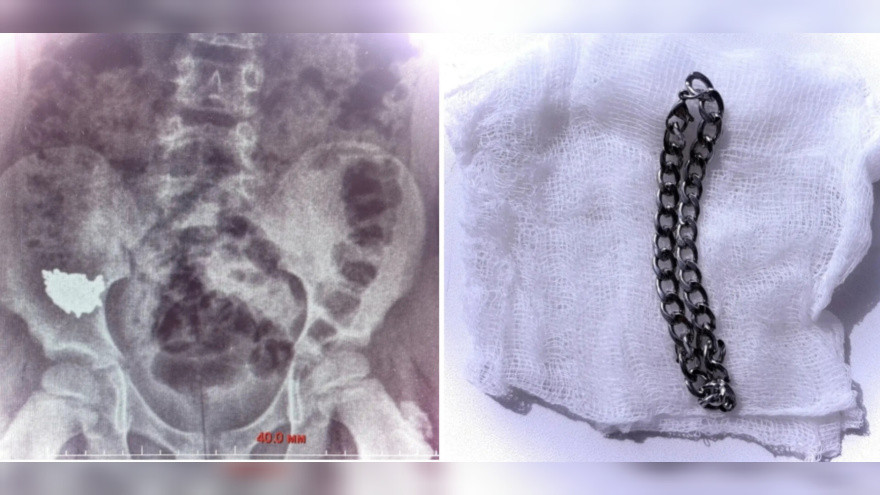

Во вторник, 7 апреля, министерство здравоохранения Воронежской области сообщило о случае с школьником, который во время игры проглотил 20‑сантиметровую цепочку.

Родители ребёнка обратились в детскую больницу № 2, после чего его госпитализировали. По словам детского хирурга Владимира Кораблёва, снимки, сделанные на третьи и четвёртые сутки после обращения, показали: инородное тело не продвигается по желудочно‑кишечному тракту и остаётся без динамики в правой подвздошной области — части тела, расположенной внизу живота.

Из‑за высокого риска перфорации кишки (образования отверстия в органе) и развития перитонита — воспаления брюшины при попадании кишечного содержимого — врачи приняли решение провести срочную операцию. Пациенту под общим наркозом выполнили колоноскопию. В результате инородное тело удалось извлечь через просвет аппендикса.